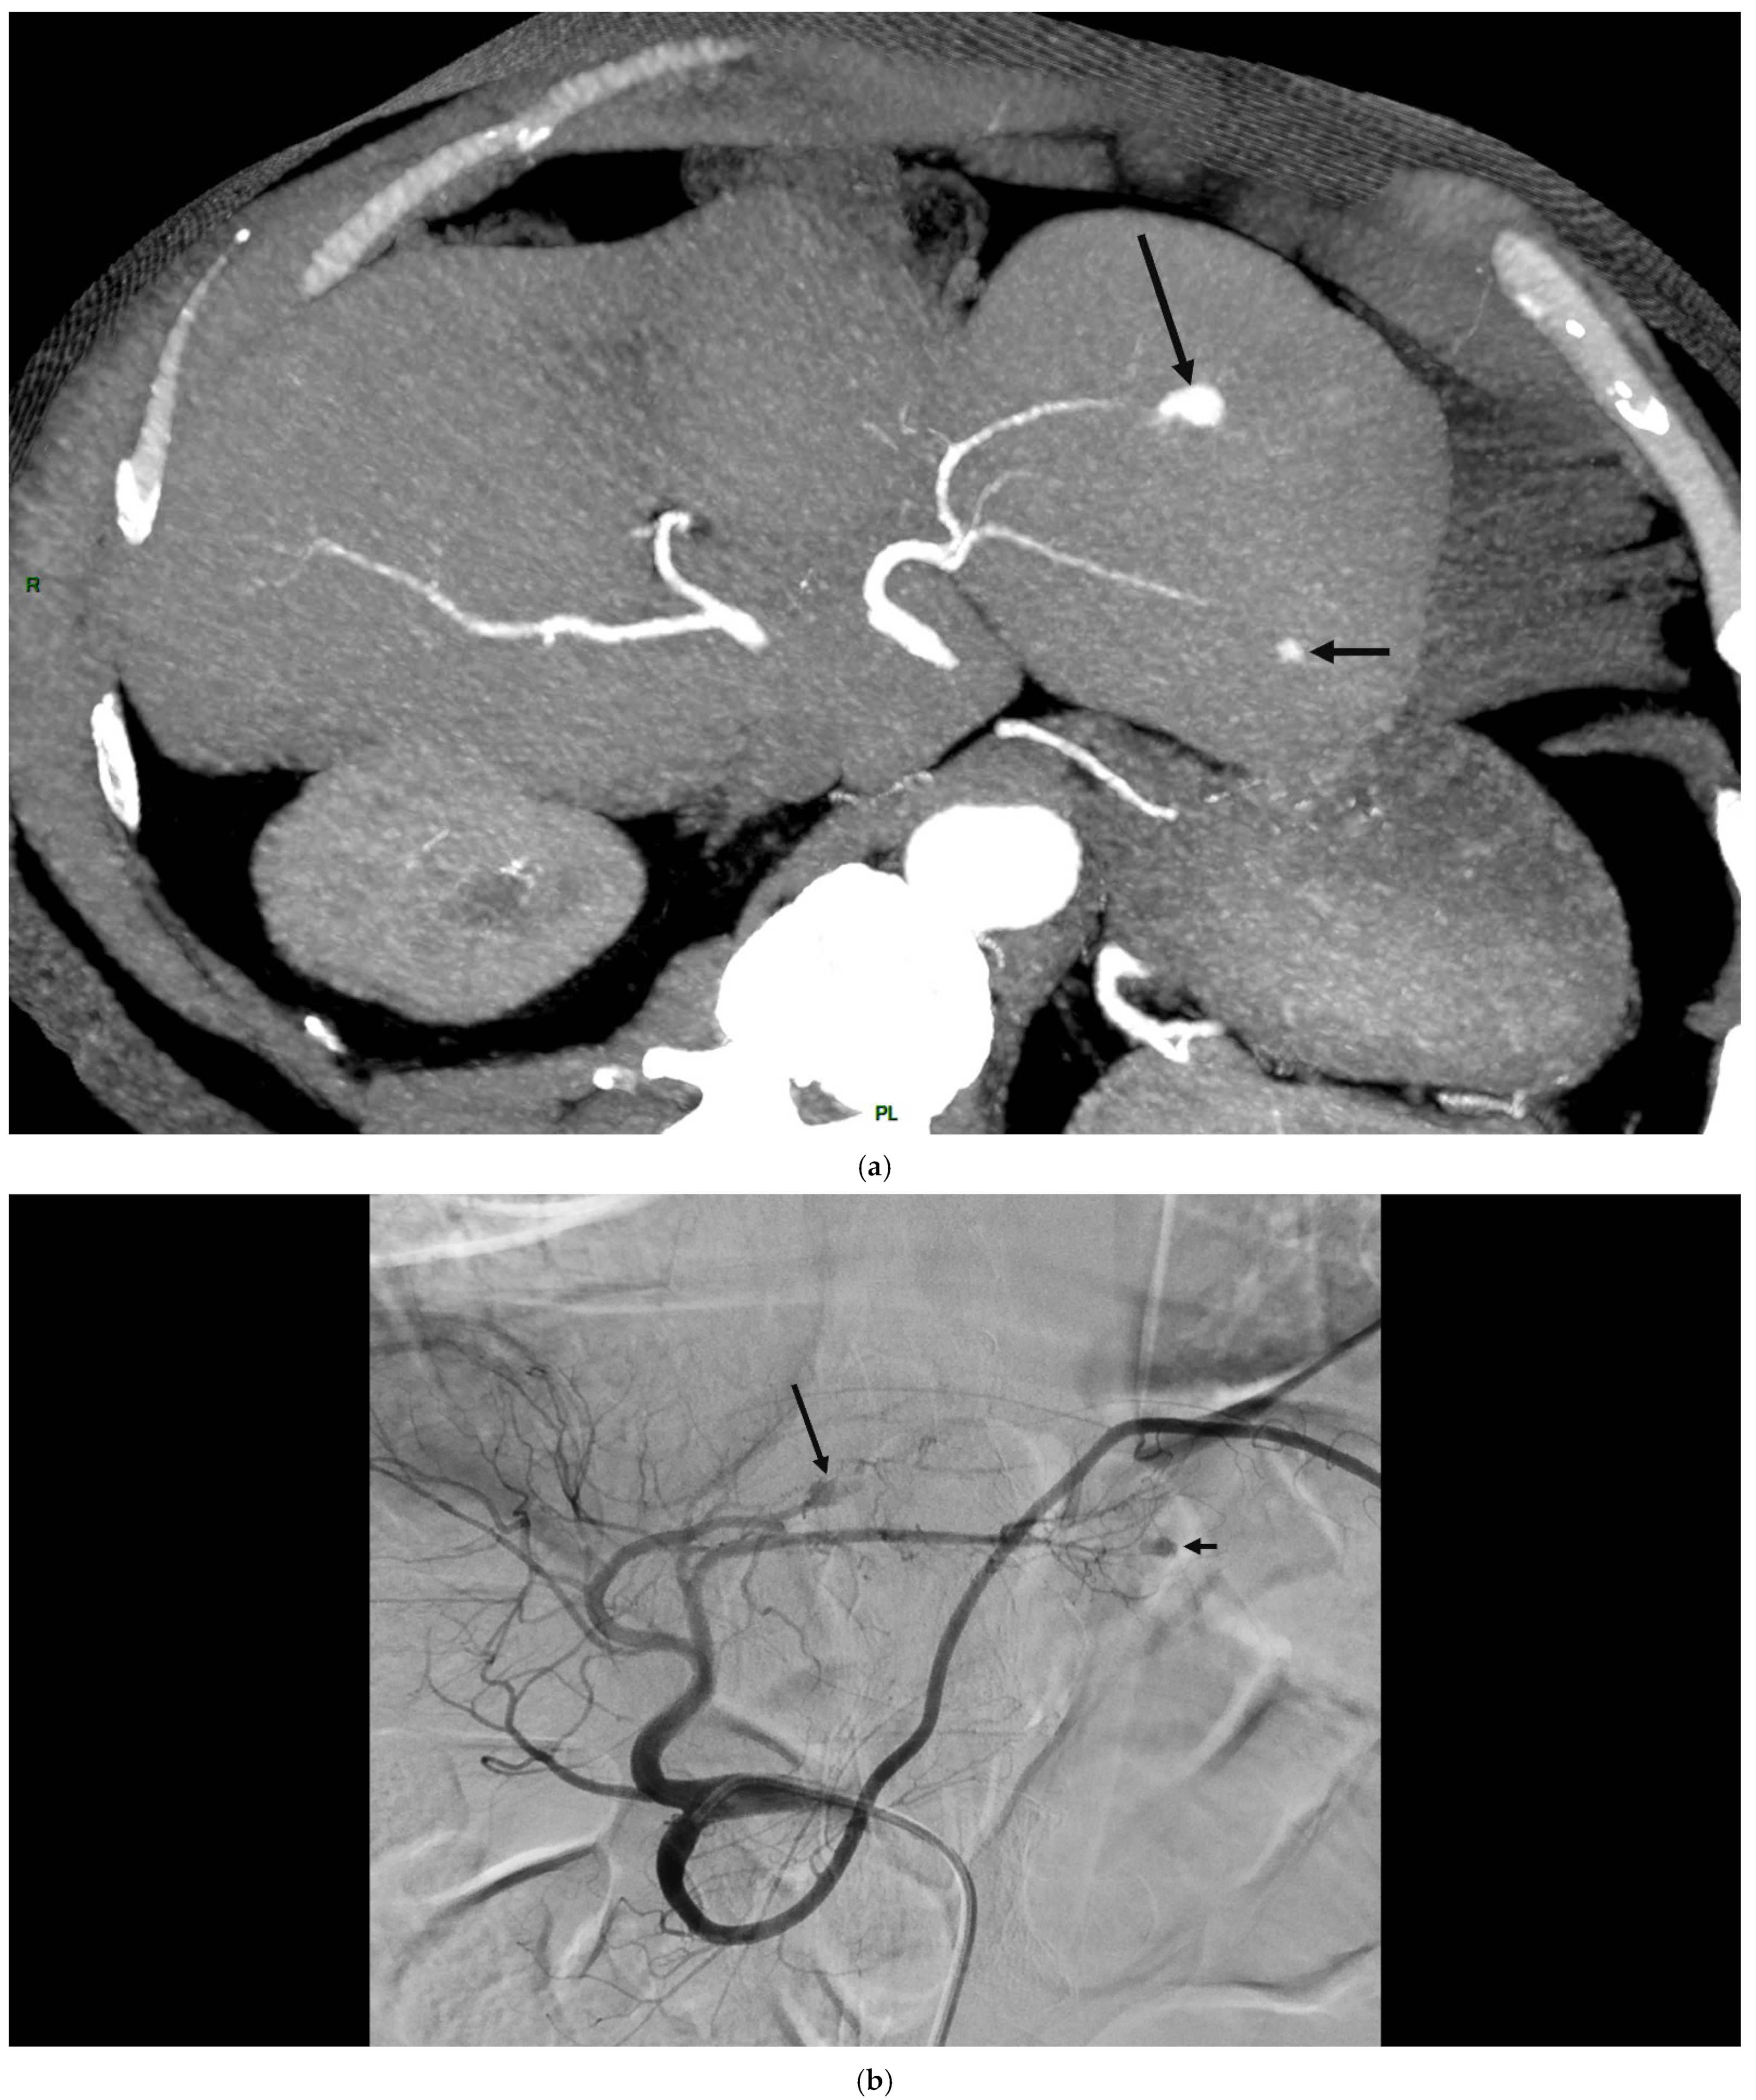

4. Clinical Characteristics of VIAs-Patients